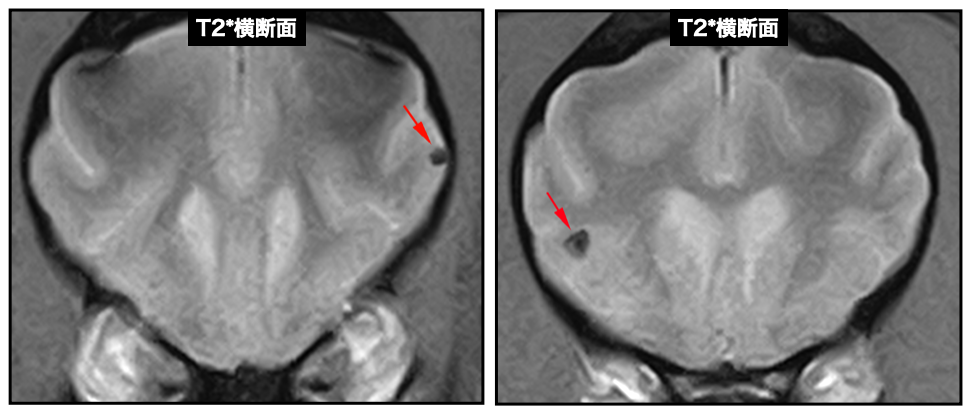

小脳梗塞を疑った11歳のトイ・プードル、症状は左前後肢が突っ張る事による起立困難